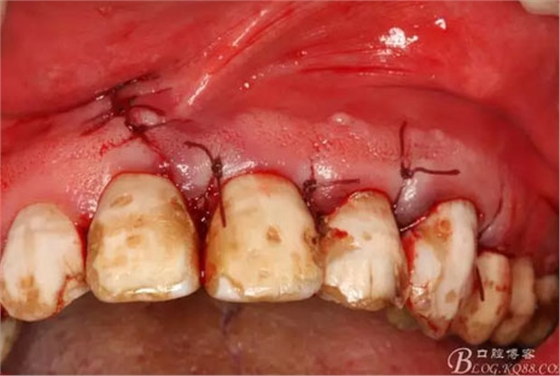

圖17.超聲骨刀根尖切除+倒預(yù)備根管

圖18.MTA倒充填完成根尖區(qū)域

圖19.縫合